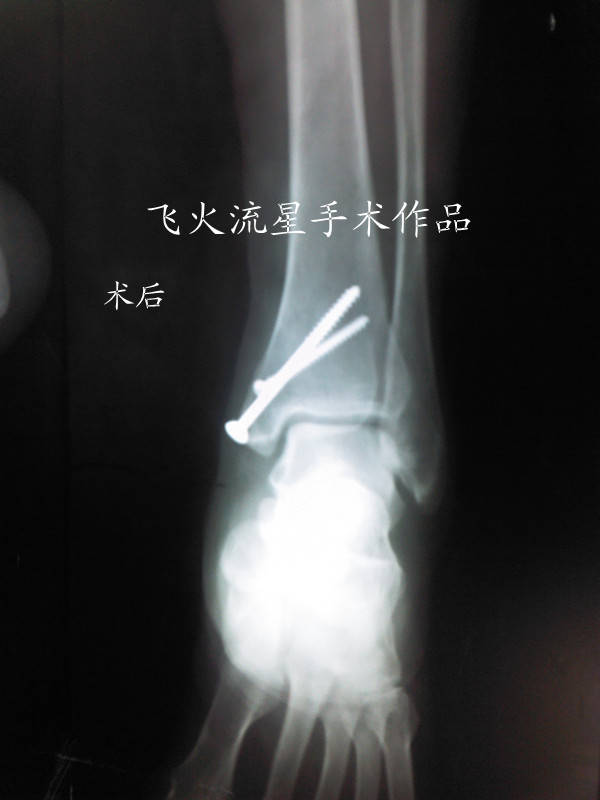

腓骨下面的三颗固定镙钉进入关节了,病人恢复期会影响关节活动的,要更换短的镙钉。

打的钉子很一般,外踝板不够贴的不进,骨折端没解剖复位,应该打个拉力螺钉,而且外踝板远端钉子有点长,感觉内踝固定不稳定,踝穴看的还凑乎。建议石膏固定一周,要不内踝会出问题,个人愚见

“外踝板远端钉子有点长”不同意你的观点,钉子不长啊,内踝固定钉位置确实欠佳。石膏固定6周。

拍个踝穴位看看肯定快到关节面了

拍个踝穴位片当然好看了,但片子上略长一点外,别的钉长短恰到好处啊!

拍个踝穴位片当然好看了,但片子上最下面钉略长一点外,别的钉长短恰到好处啊!

内踝的螺钉很危险啊?!!!